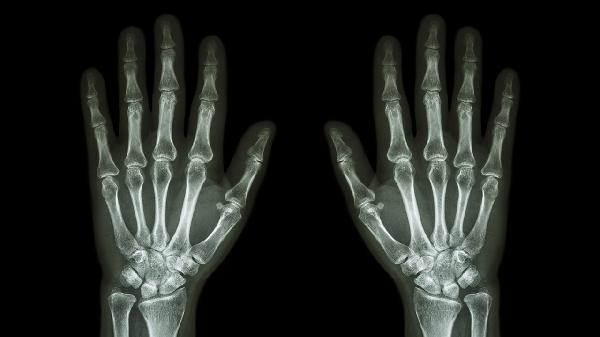

中老年人群多见,与关节软骨退化相关。晨起关节僵硬感明显,弯曲时出现摩擦音,X线可见关节间隙变窄。治疗需控制体重减轻关节负荷,配合硫酸氨基葡萄糖胶囊、玻璃酸钠注射液等软骨保护剂。疼痛发作时可短期使用洛索洛芬钠贴剂局部外敷。